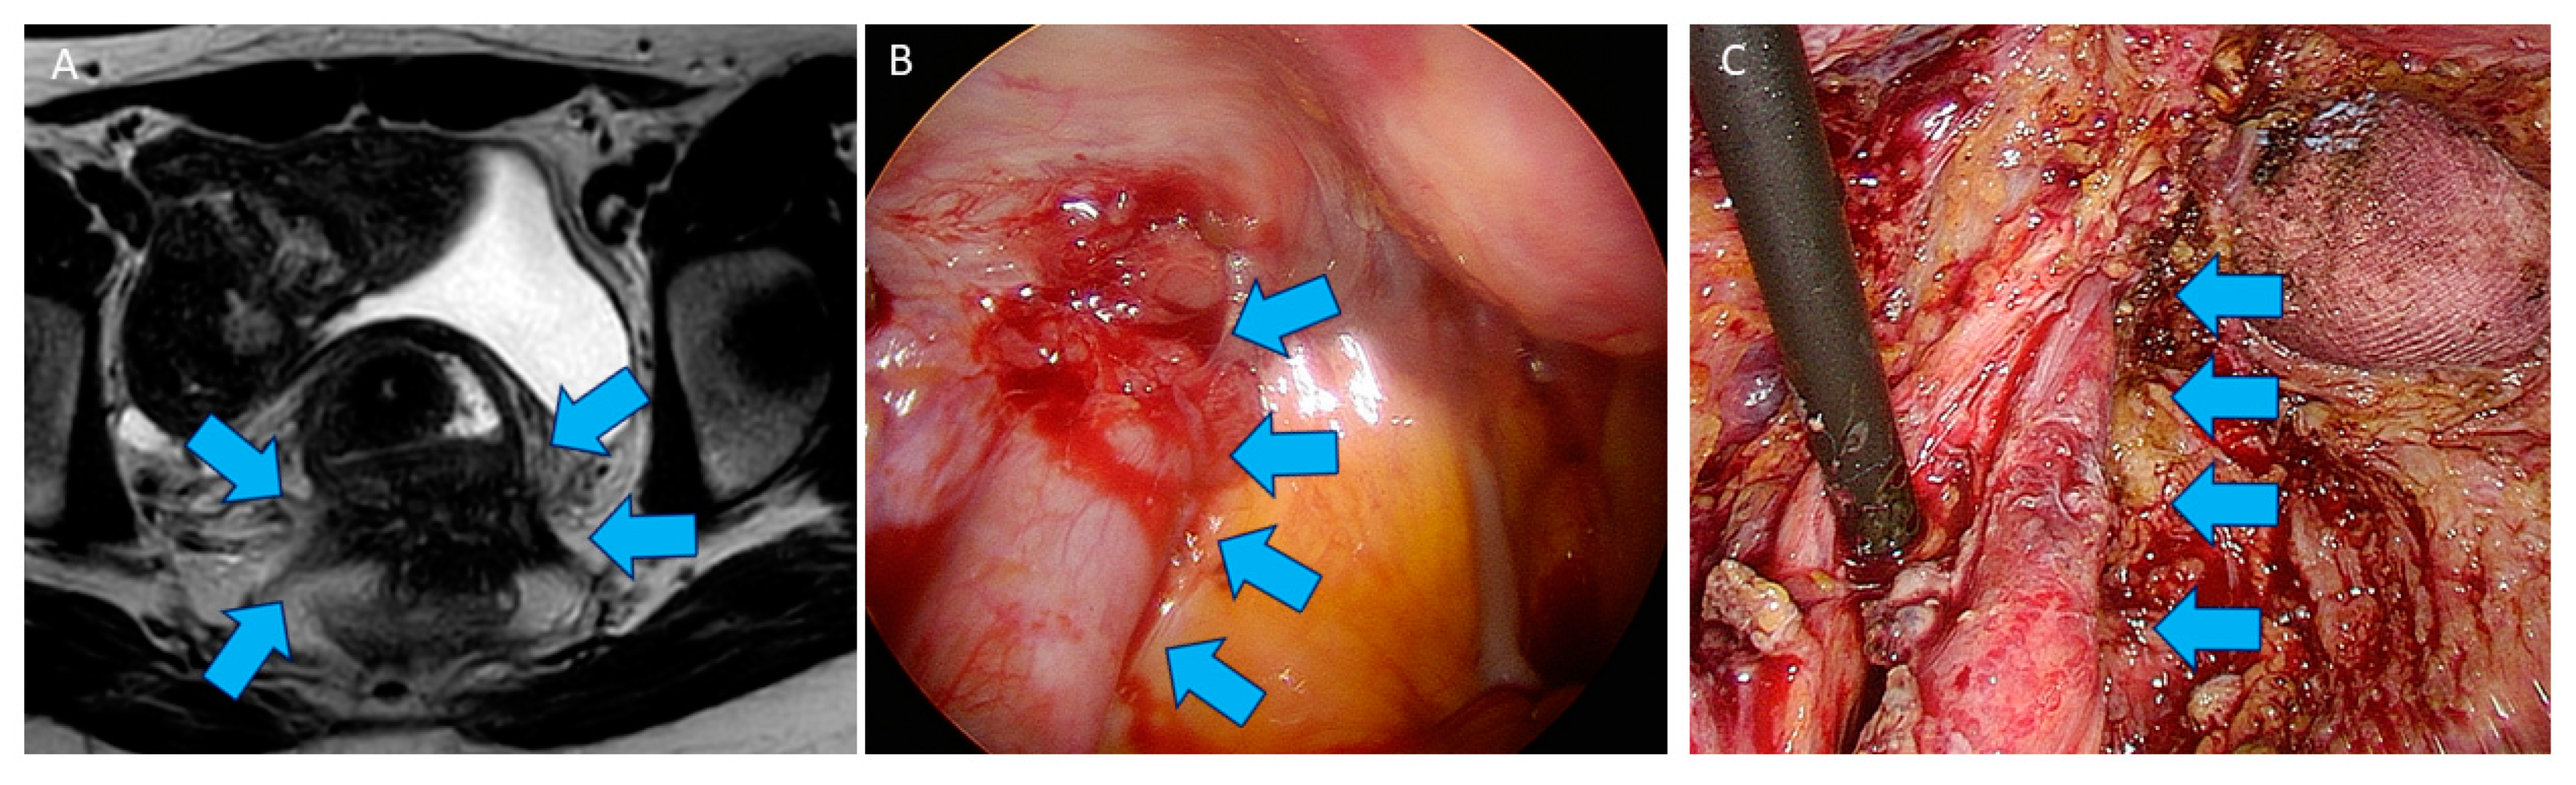

- Bazot, M.; Bharwani, N.; Huchon, C.; Kinkel, K.; Cunha, T.M.; Guerra, A.; Manganaro, L.; Buñesch, L.; Kido, A.; Togashi, K.; et al. European society of urogenital radiology (ESUR) guidelines: MR imaging of pelvic endometriosis. Eur. Radiol. 2017, 27, 2765–2775. [Google Scholar] [CrossRef]

- Bazot, M.; Kermarrec, E.; Bendifallah, S.; Daraï, E. MRI of intestinal endometriosis. Best Pract. Res. Clin. Obstet. Gynaecol. 2021, 71, 51–63. [Google Scholar] [CrossRef] [PubMed]

- Koninckx, P.R.; Ussia, A.; Adamyan, L.; Wattiez, A.; Donnez, J. Deep endometriosis: Definition, diagnosis, and treatment. Fertil. Steril. 2012, 98, 564–571. [Google Scholar] [CrossRef]